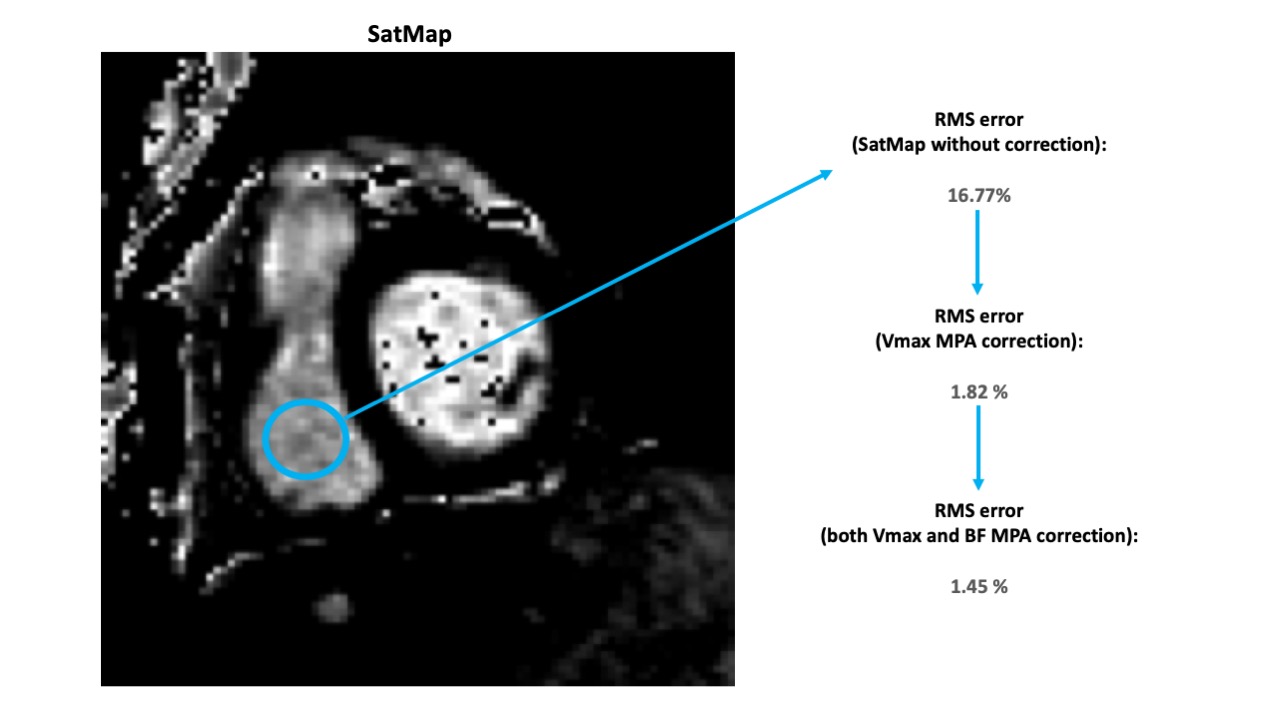

Figure 3. An example of the corresponding SatMap, with a region of interest (ROI) placed within the right ventricular cavity to extract blood values, shows root mean square (RMS) error decreasing from 16.77% without correction, to 1.82% with Vmax correction, and to 1.45% with both Vmax and BF corrections.